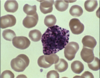

3

Q

A

basophil

4

Q

A

basophil